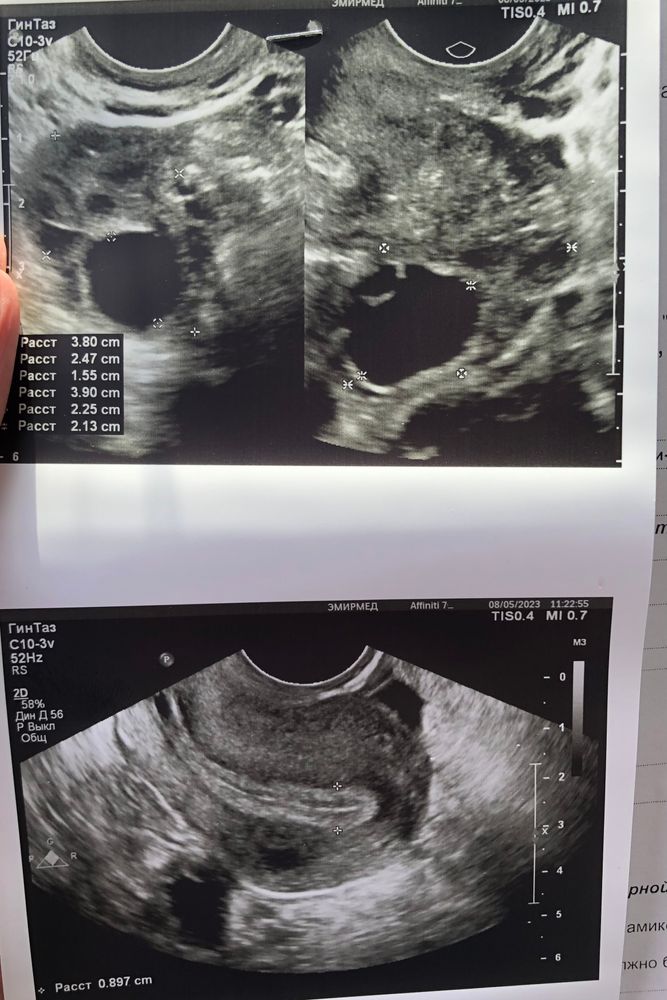

Сегодня с мужем сдавали анализы для вми, поставила последний укол Менопур и решила фолликулометрию сделать . Фото ниже.

Теперл думаю , ставить ли укол хгч, в левом уже созрел фоллик((

Уже хороший,зрелый и эндометрий трёхслойный,думаю завтра самое то кольнуть) в день на 2 мм растёт ,как раз завтра будет его пик

Juliya, второй маловат ,не успеет вырасти,а этот самое то. У меня в этот раз 19 дорос, врач отправила на следующей день ставить укол , только сказала обязательно к вечеру)

Я б сегодня вечером уколола. Им ещё 36 часов в среднем дозревать до О, как раз и мелкий подтянется быстрее и одновременно лопнут.